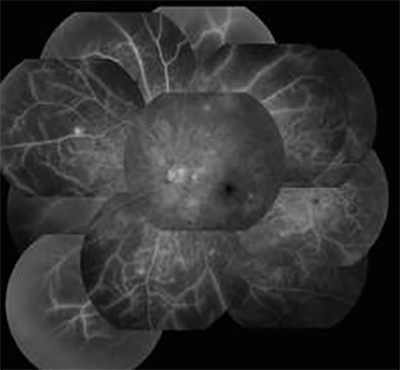

網膜光凝固の必要な症例

造影剤で中心から外れた部分が造影剤がまったく届かず、血管以外黒く抜けてみえます。中心部は比較的正常に近いので自分ではおかしくないようにみえるのですが、気づかないうちに悪化している症例です。こういう症例では網膜光凝固しておき、網膜を間引きしておく方が失明から遠ざかります。